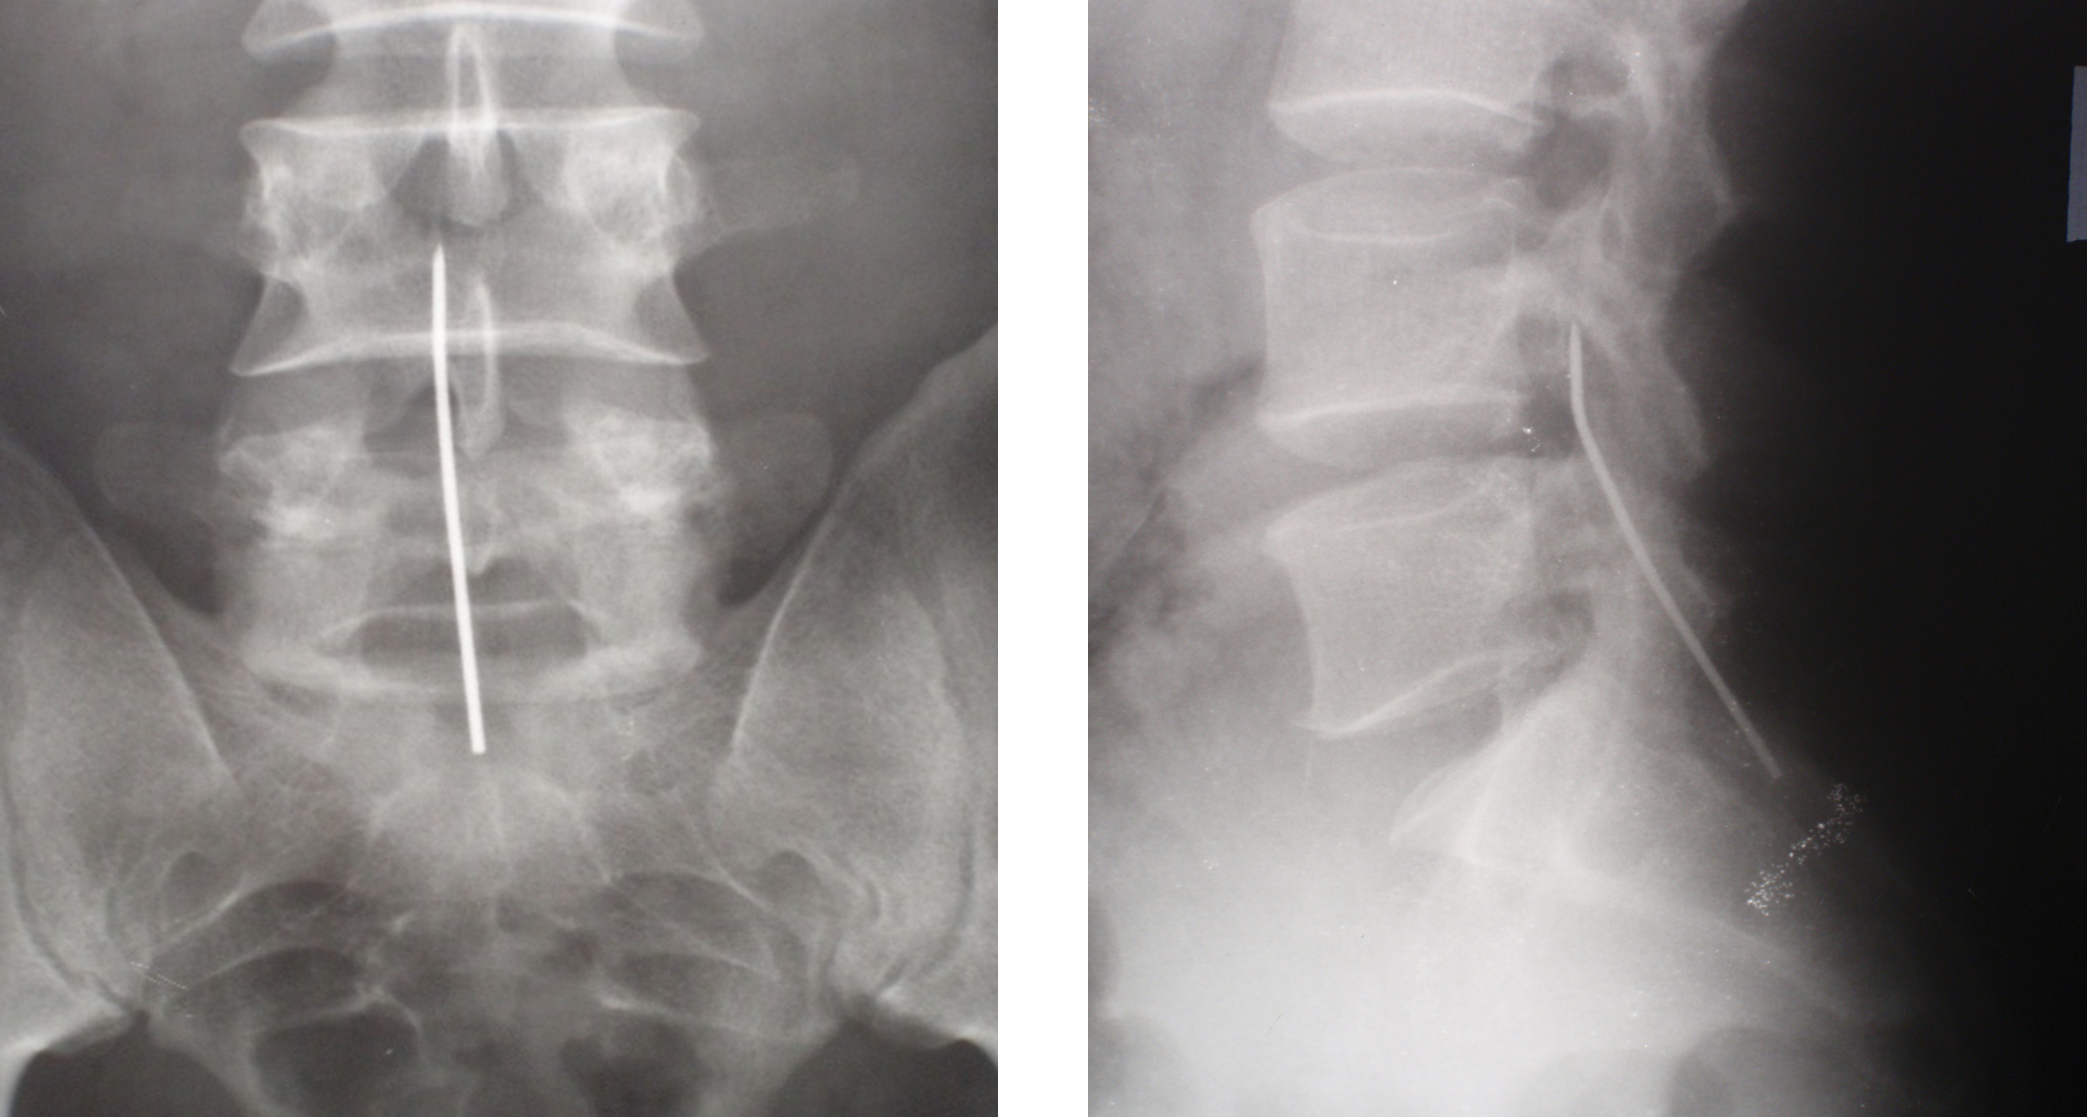

In 2011, a 32-year-old patient B. came to the clinic with complaints of pain in the coccyx area. An X-ray examination revealed a foreign body in the patient's lumbar-sacral spine region, a 6-cm-long fragment of a Kirschner wire. (Fig. 1).

Figure 1. X-ray images of the lumbar-sacral spine of patient B. The foreign body is a fragment of a Kirschner wire

From the anamnesis, it was found out that in 1999, the patient was operated on in another clinic for damage to the acromioclavicular joint on the right. Osteosynthesis was performed with two crossed Ktrshner wires. After 4 weeks, postoperative immobilization was stopped, and the patient was discharged to work, but the wires were not removed. In 2009, the patient experienced pain in the neck for several months. The neurologist prescribed treatment, including massage, and the pain gradually subsided.

Figure 2. X-ray of the right shoulder joint of patient B. Fracture of the spokes and absence of one of the proximal fragments.